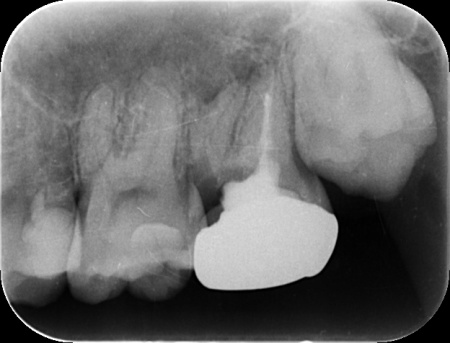

矯正治療により、親知らずが歯並びのラインに収まってきたところで、歯根の先端を手前側に起こす力を与えるためにワイヤーをかけ、歯を移動させながら歯列が平行になるように調整します。

後日歯並びが整ったことを確認し、治療を終了しました。